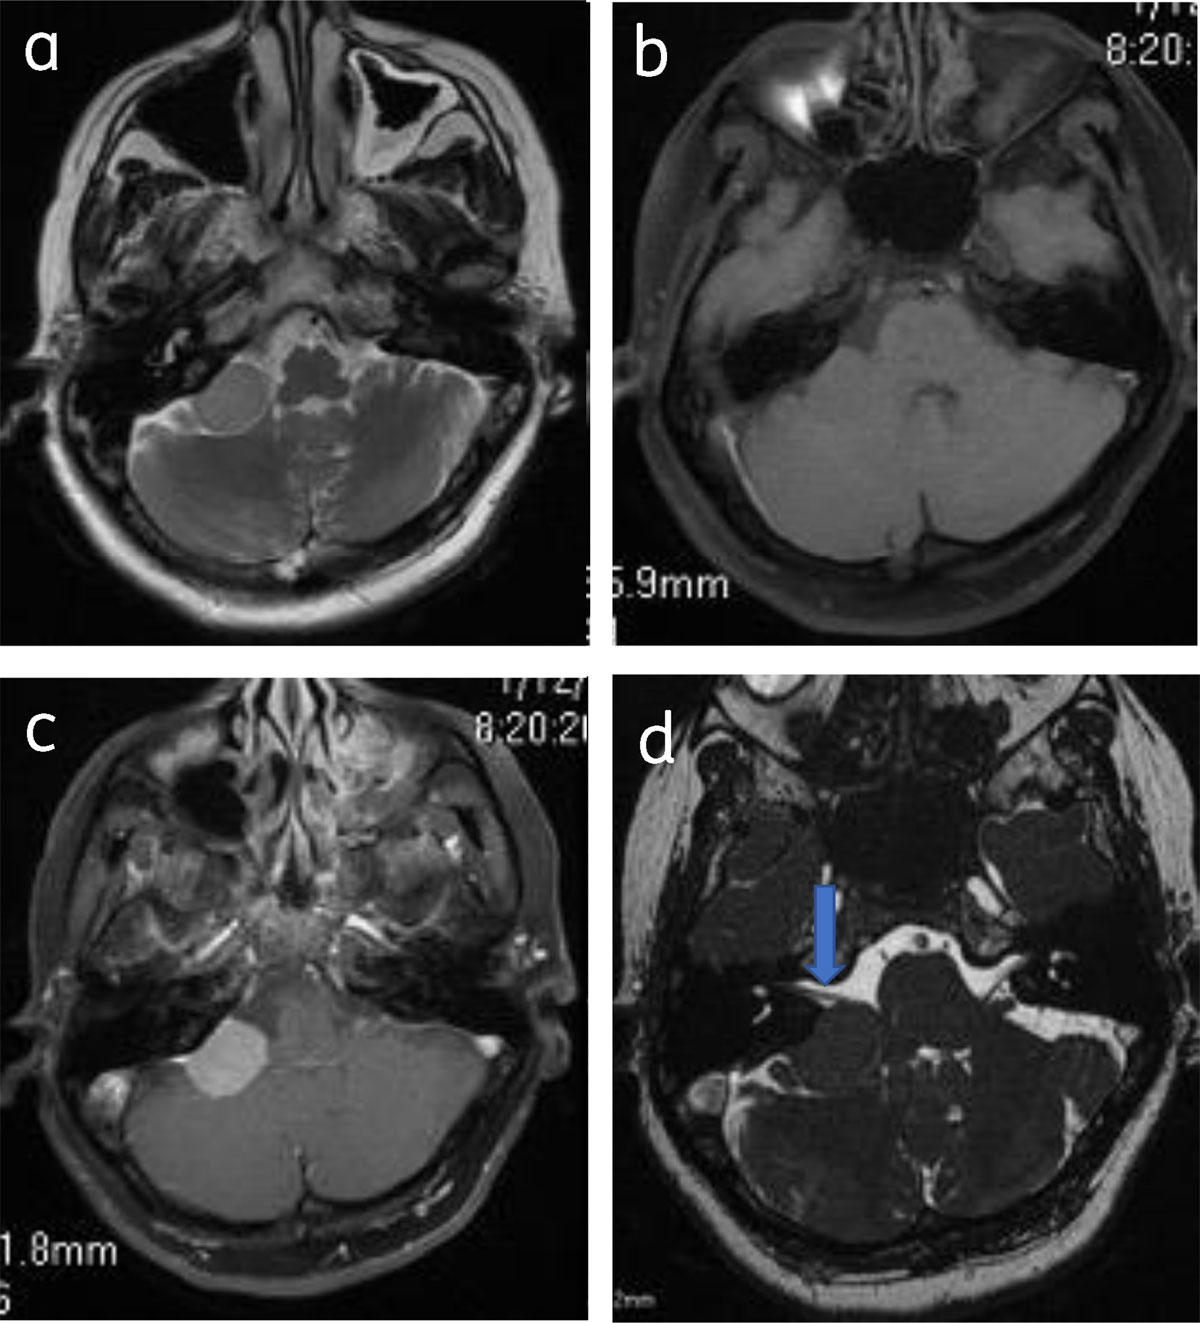

Classical Meningioma are extra axial and broad based, appear hypo-isointense on T1WI and iso-hyperintense on T2WI to the gray matter, and show intense homogenous contrast enhancement (Figure 1).

Figure 1

Classical meningioma: – (a) Axial post contrast image show enhancing broad based extra-axial lesion (star). Lesion is isointense on T2W (b) and T1W (c) to the gray matter.